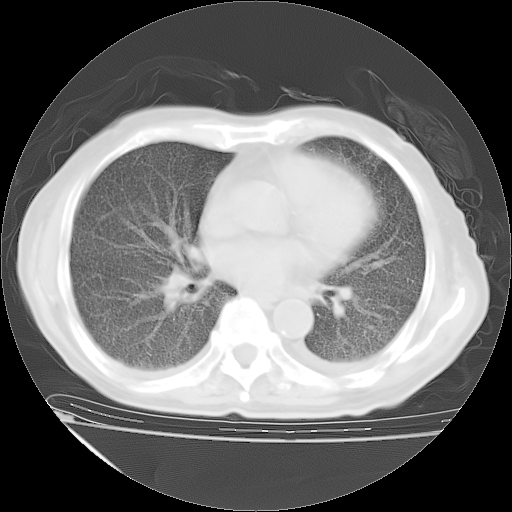

经过24天治疗,岳父的病情基本稳定。生活基本可以自理,可以下床活动。呼吸困难早已消失。体温基本正常。

只是甲强龙用80mg时血小板升到正常,改为60mg后又降到63×10*9/L。

主要治疗甲强龙80mg×14天,60mg×10天;同时抗结核(异烟肼+利福平+乙胺丁醇)。环磷酰胺0.1 tid 10天。

特别感谢胡教授、高管、桃子版主给出关键的治疗建议。桃版把所有肺部影像和全部临床资料请所在医院呼吸科、感染病科、结核科、临床免疫科专家会诊。临床免疫科专家制定了完整的治疗方案。